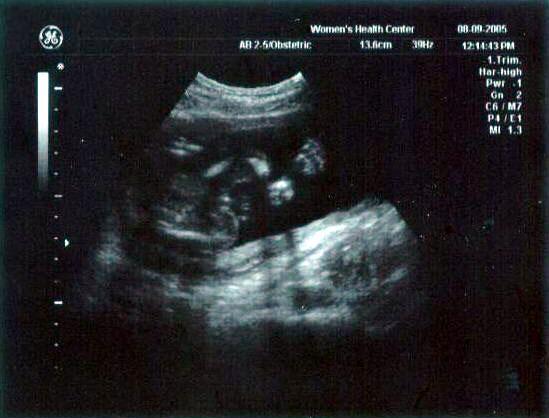

13 week ultrasound ~ The little one's getting bigger!